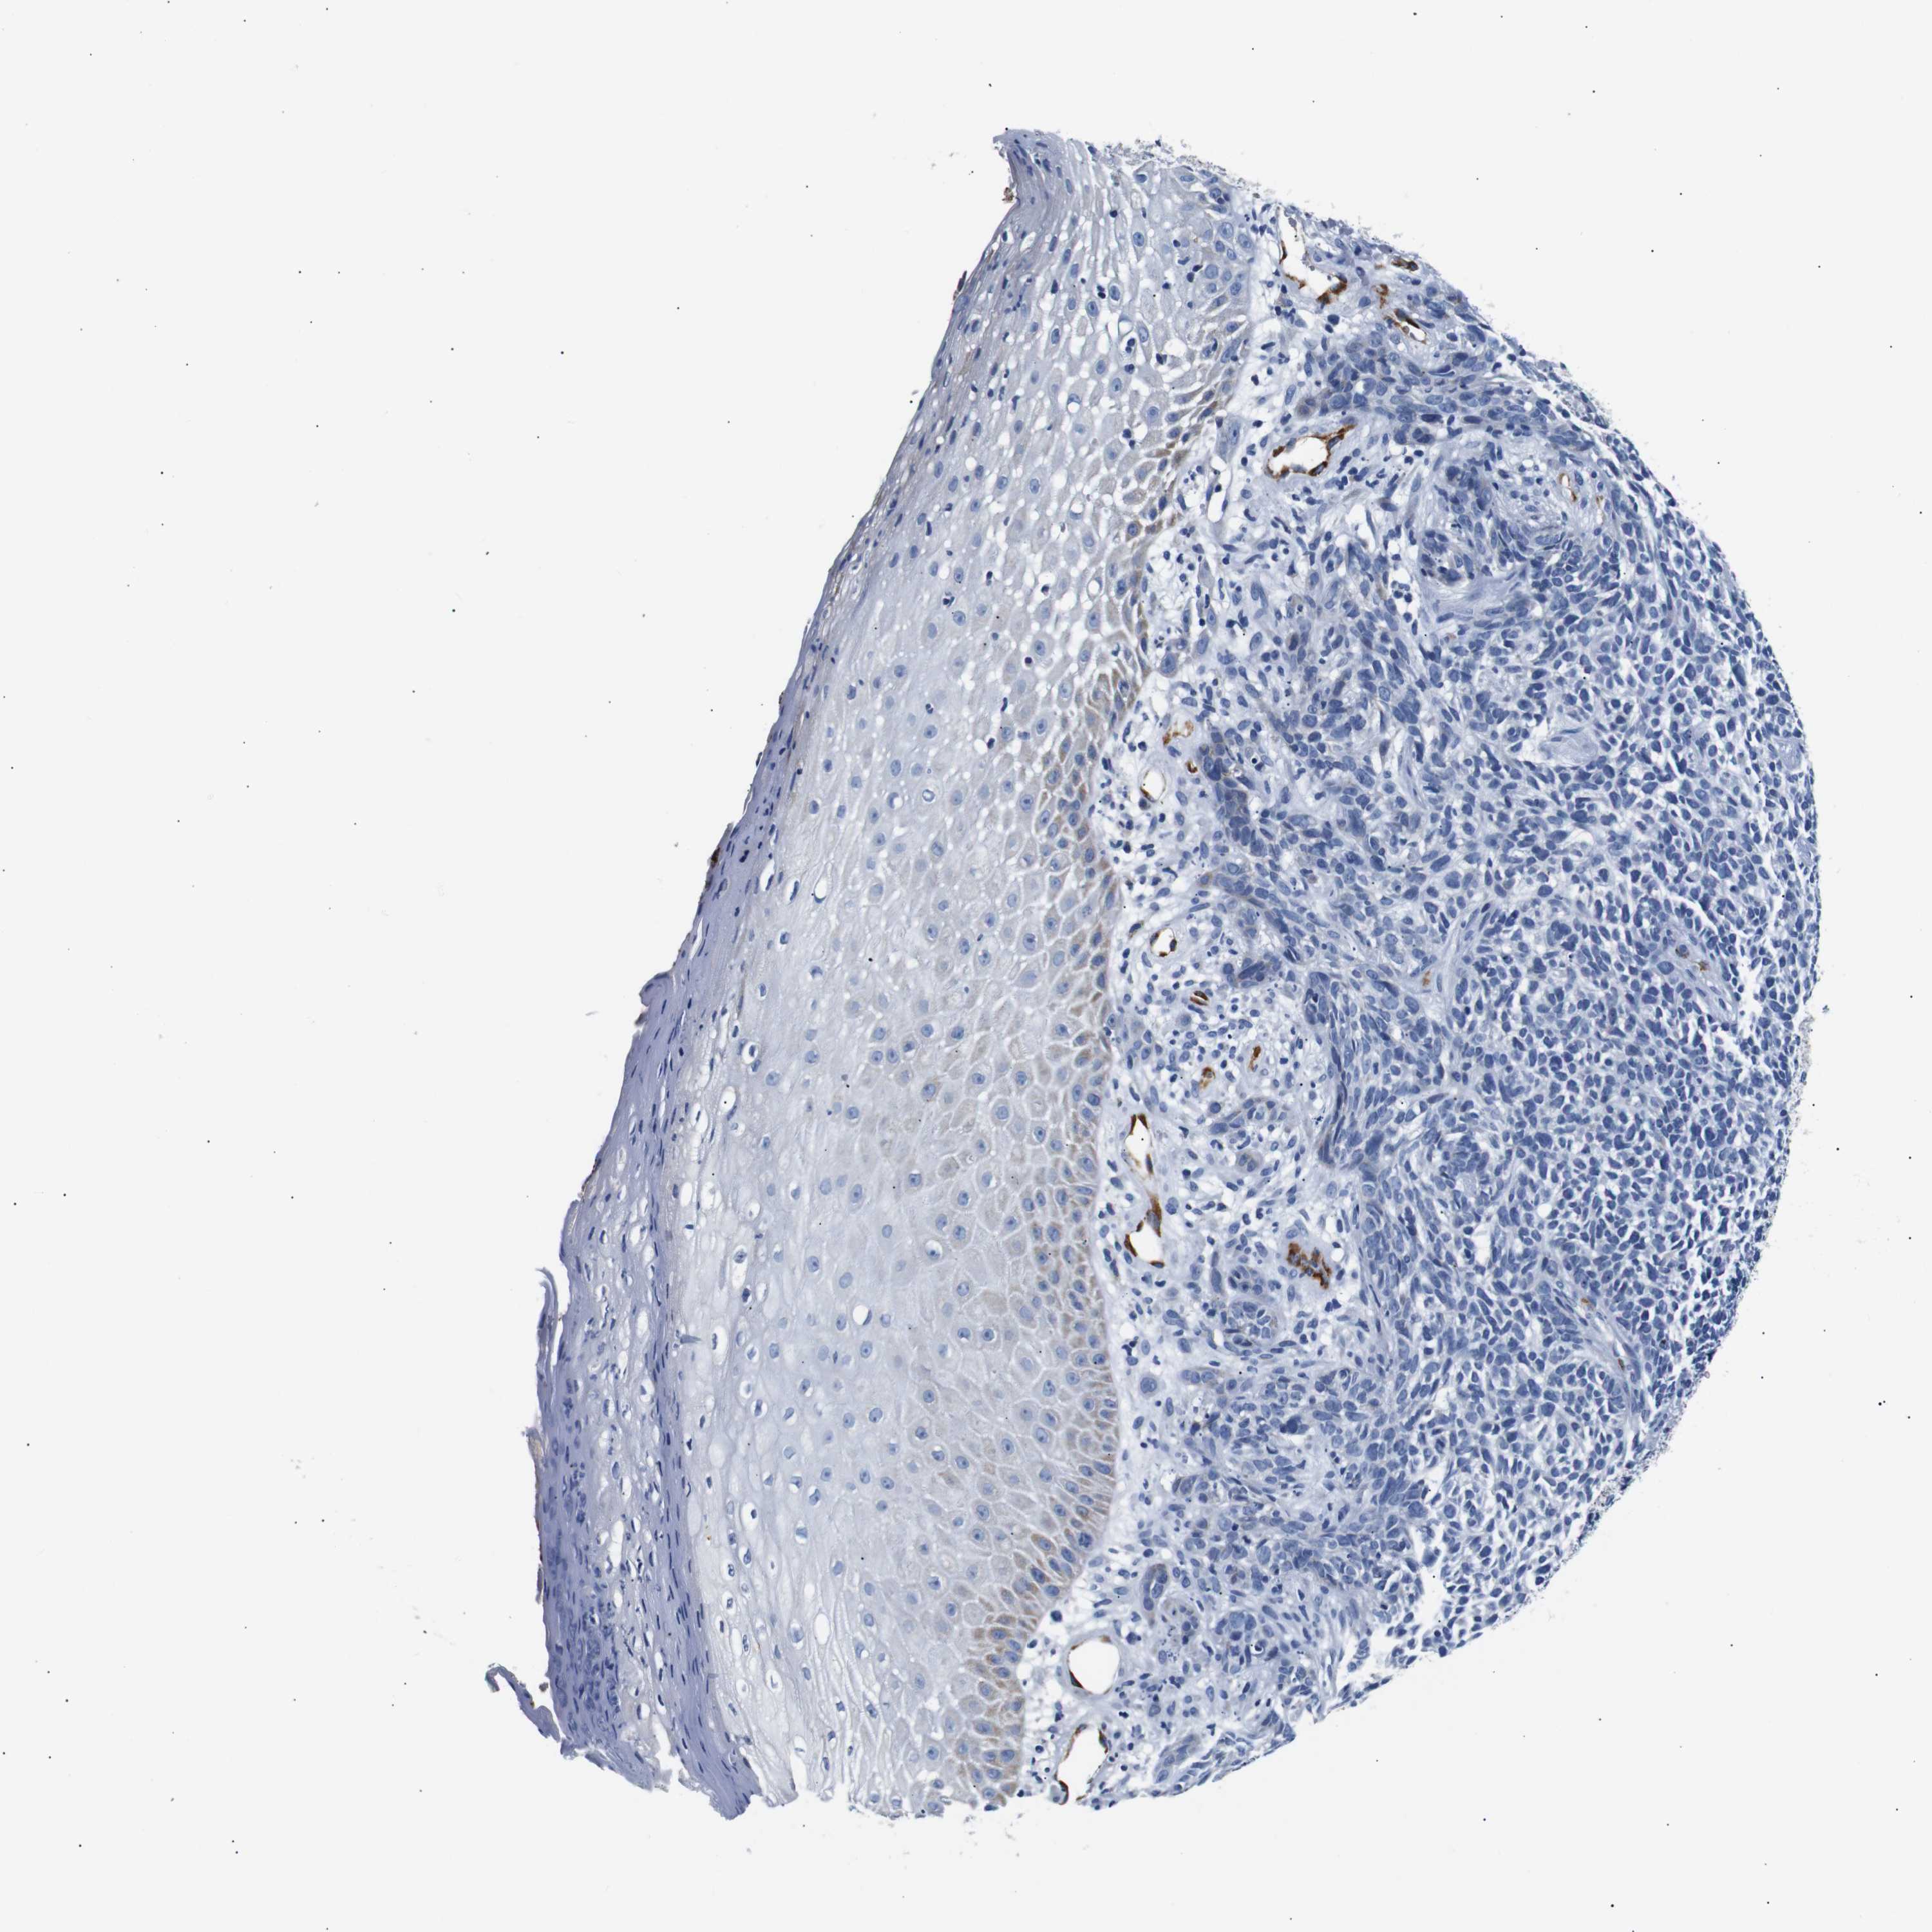

SKIN CANCER - Protein expressioni

A mouse-over function shows sample information and annotation data. Click on an image to view it in a full screen mode. Samples can be filtered based on level of antibody staining by selecting one or several of the following categories: high, medium, low and not detected. The assay and annotation is described here.

Antibody stainingi

Antibody staining in the annotated cell types in the current human tissue is reported as not detected, low, medium, or high, based on conventional immunohistochemistry profiling in selected tissues. This score is based on the combination of the staining intensity and fraction of stained cells.

Each image is clickable and will lead to virtual microscopy that enables deeper exploration of all samples and also displays staining intensity scores, fraction scores and subcellular localization as well as patient and tissue information for each sample.

Antibody HPA005895

Antibody CAB013536

Squamous cell carcinoma, NOS

Basal cell carcinoma